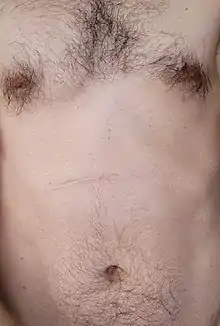

The definitive treatment of pyloric stenosis is with surgical pyloromyotomy known as Ramstedt's procedure (dividing the muscle of the pylorus to open up the gastric outlet). This surgery can be done through a single incision (usually 3–4 cm long) or laparoscopically (through several tiny incisions), depending on the surgeon's experience and preference.[20]

Today, the laparoscopic technique has largely supplanted the traditional open repairs which involved either a tiny circular incision around the navel or the Ramstedt procedure. Compared to the older open techniques, the complication rate is equivalent, except for a markedly lower risk of wound infection.[21] This is now considered the standard of care at the majority of children's hospitals across the US, although some surgeons still perform the open technique. Following repair, the small 3mm incisions are hard to see.

The vertical incision, pictured and listed above, is no longer usually required, though many incisions have been horizontal in the past years. Once the stomach can empty into the duodenum, feeding can begin again. Some vomiting may be expected during the first days after surgery as the gastrointestinal tract settles. Rarely, the myotomy procedure performed is incomplete and projectile vomiting continues, requiring repeat surgery. Pyloric stenosis generally has no long term side-effects or impact on the child's future.